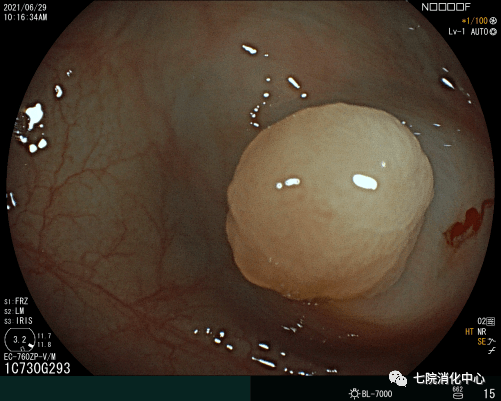

3、EMR:

常用于切除无蒂息肉 , 通过注射缓冲液到黏膜下层的空间 , 使上皮与底层组织分开 , 使病变分离 。 包括整块切除和分次切除 , 目前黏膜下注射切除法是最常用的一种EMR切除法 , 其他EMR切除方法还有透明帽辅助EMR、注水法/水下法EMR等 , EMR在实现大肠息肉的完整内窥镜切除术方面明显优于冷圈套器 , 但它需要黏膜下注射和电灼 , 因此不可避免出现延迟出血、息肉切除术后综合征和穿孔等并发症 。